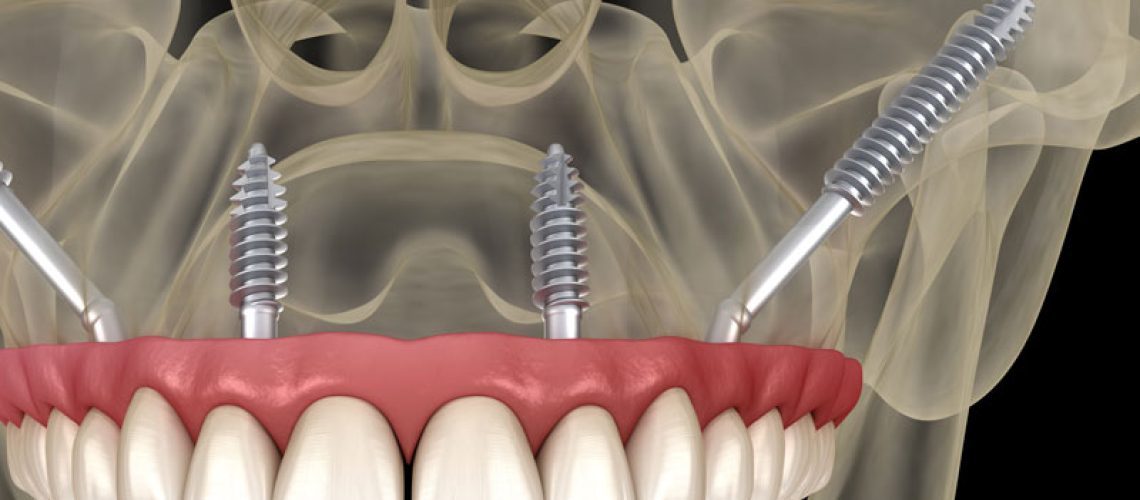

Understanding The Zygomatic Arch

Zygomatic implants are implants placed within the zygomatic arch. This arch is located further up from your maxilla, the upper jawbone, closer to your eyes. Think your cheekbones and you are in the right ballpark area.

This area of the face is great for stability as it is not impacted by the same bone loss that the maxilla is affected by in oral health. This means those with severe bone loss are able to have this implant done still with minimal to no bone grafting.